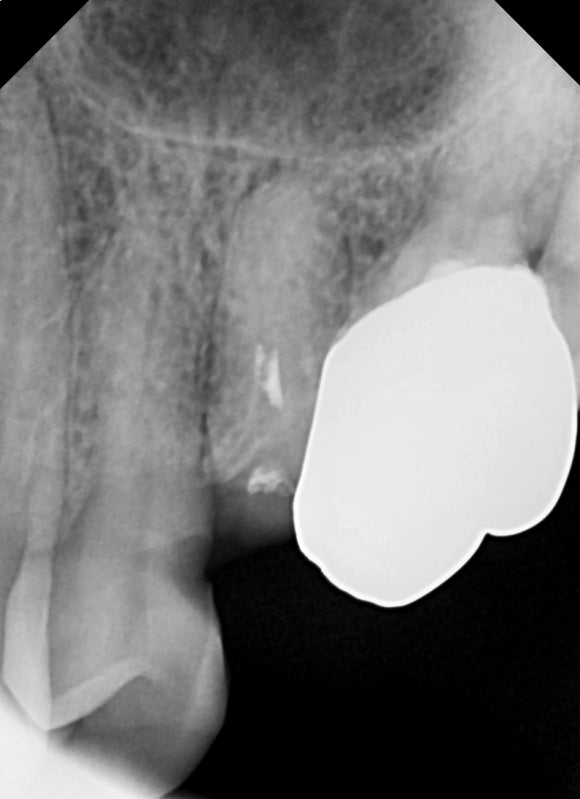

20250311

크라운이 접착될 치아 부분이 확보되는 것이 중요합니다.

따라서 잇몸을 조금 성형하여

크라운을 지지할 수 있을만큼의 치아 높이를 확보해줍니다.

치은절제술이라고도 불리는 시술인데

국소마취하에 진행하기 때문에 아프지도 않고

마취가 풀려도 크게 불편하지 않습니다.

가끔 해당 부위가 며칠 욱신거리거나 쓰라리다고 말씀하시는 분들도 계십니다.